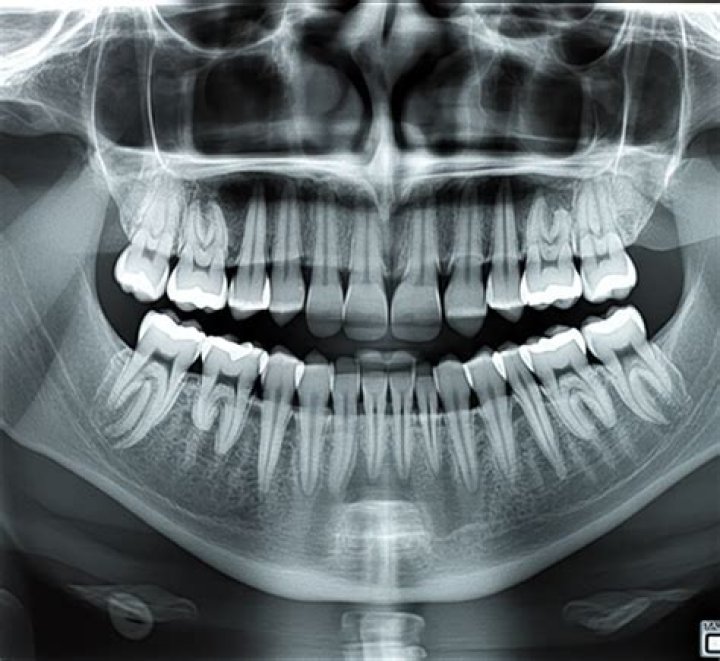

What does a dental X-ray show?

Dental X-rays are pictures of the teeth, bones, and soft tissues around them to help find problems with the teeth, mouth, and jaw. X-ray pictures can show cavities, hidden dental structures (such as wisdom teeth), and bone loss that cannot be seen during a visual examination.